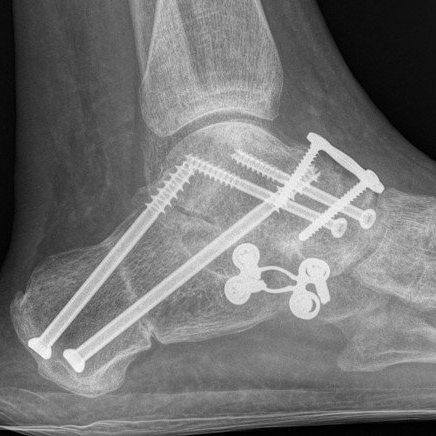

Fusion is permanently stiffening

the bones of a joint together with plates, screws and/or staples. This procedure is also known as arthrodesis.

This surgical procedure involves fusing one or more of the midfoot and hindfoot joints. A common combination is called a hindfoot "triple fusion".